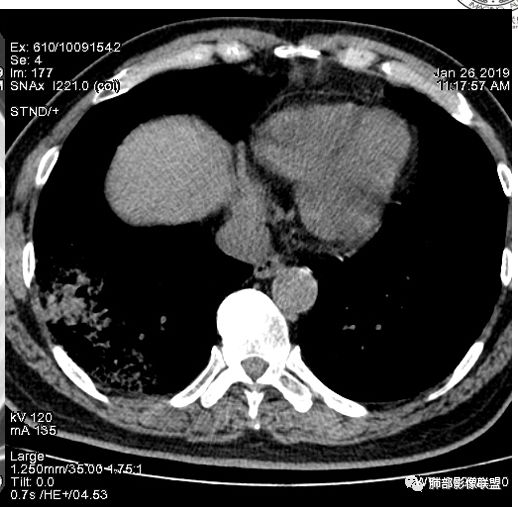

老年女性,右肺下叶沿胸膜下大片状高密度影,外周磨玻璃影,边界较清,内可见蜂窝征及支气管充气征,考虑肺炎型肺癌。

老年女性,咳嗽咳痰病史,右肺下叶大片磨玻璃实变影,胸膜下分布,支气管进入后扩张、僵直,磨玻璃影边界清楚,考虑粘液腺癌。鉴别肺炎。

右肺下叶基底段靠胸膜实变/磨玻璃混杂密度影,边界清楚,内见多发空泡(蜂窝样趋势改变?); 临床:咳嗽咳痰,无发热、胸痛; 考虑腺癌:无发热,感染性病变不首先考虑;部分层面形态类楔形,鉴别肺栓塞

老年女性,右下肺实变影,病灶里有小叶内间质增厚,周围GGo,支气管扩张,粘液性腺癌?淋巴瘤?

中年女性,咳嗽咳痰。右肺下叶片状高密度影,部分实性密度,周围见边界清晰磨玻璃影,内见小空泡,实性区部分支气管堵塞,有重力效应,考虑肺炎型肺癌,建议查痰脱落细胞。

老年人,右肺下叶斑片状阴影,病灶有膨胀性,边缘可见磨玻璃影,其边界清晰,内见僵硬的支气管,部分支气管扩张,首先考虑占位性病变,粘液性腺癌可能。鉴别感染性病变,后者边缘多有收缩性改变或者平直,内部支气管走形自然。

1.本例病灶较大片混杂密度影,胸膜下分布为主(未沿着支气管分布),该分布特点可见于大叶性肺炎、干酪性肺炎、淋巴瘤及粘液腺癌等。可惜未提供增强扫描图像。

2.病灶示中央实变区,周围GGO,可见明显小叶间隔增厚,GGO边界清楚,应当考虑到恶性病变的可能性。肺炎因炎性水肿及渗出,影像上边界常模糊不清,注意早期粘液腺癌可出现似清非清的边界。粘液腺癌因粘液成份较多,密度一般偏低,纵隔窗病灶常会消隐或范围会明显缩小,这不同于炎性实变。

3.病灶内支气管走形略显僵直,侧支少(粘液阻塞),也符合肺腺癌的枯树枝征。而大叶性肺炎的支气管是管壁光整、通畅、自然,结核的支气管常常壁增厚,甚至狭窄后扩张;